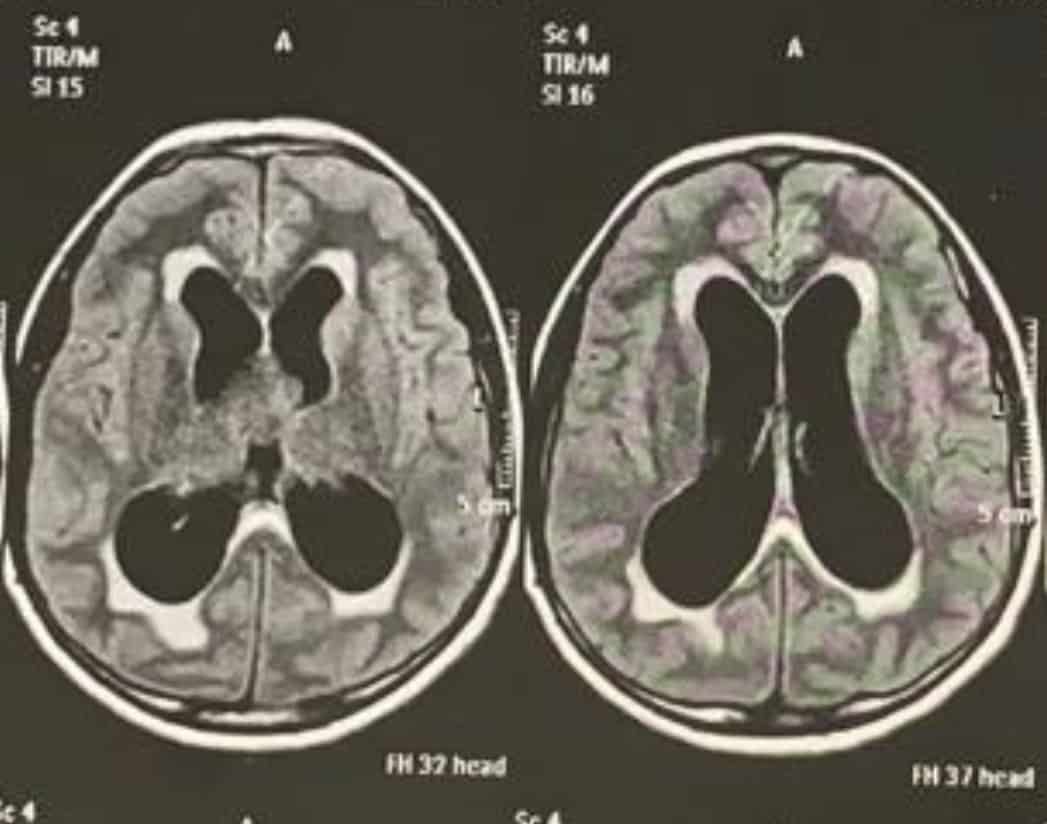

A hidrocefalia é uma doença caracterizada pelo aumento do volume e/ou pressão do líquor, o líquido contido nas cavidades do cérebro (chamados ventrículos). É uma das principais doenças que fazem com que crianças necessitem visitar um Neurocirurgião. Ela pode ser uma condição congênita, iniciada ainda no período fetal ou adquirida ao longo da vida, em qualquer fase.

Esse acúmulo gera sintomas diferentes dependendo da idade. No primeiro ano de vida, o sintoma mais evidente é o aumento progressivo e desproporcional do tamanho da cabeça. Em pacientes mais velhos, causa aumento da pressão dentro do crânio e leva a vários sintomas como dor de cabeça, vômitos, alterações de comportamento, atraso no desenvolvimento, dificuldade de andar, perda de controle da urina e, em casos mais agudos e graves, coma e morte.